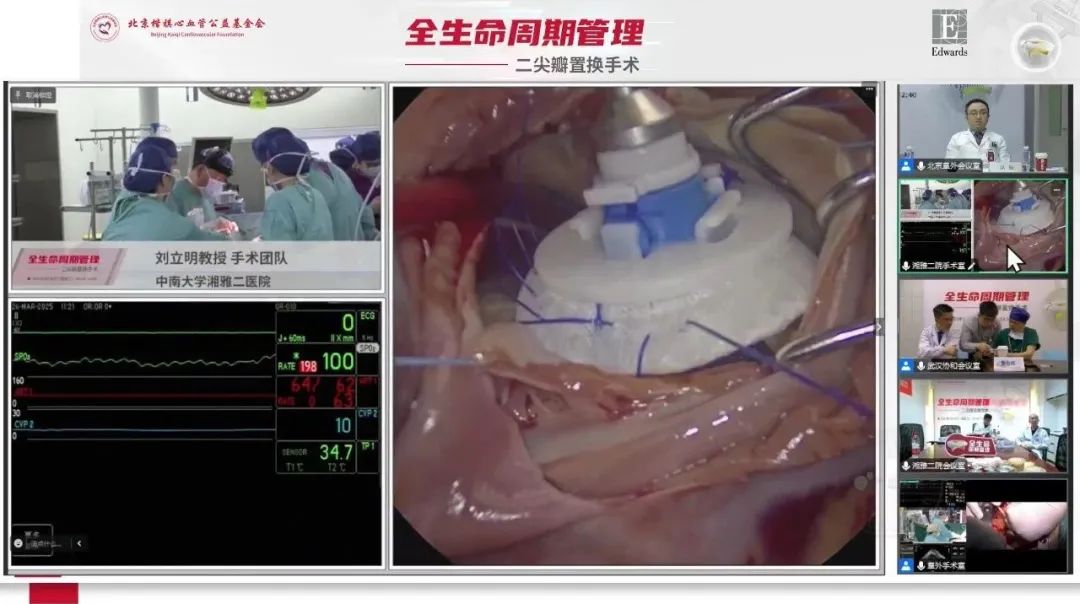

2025年3月26日,全生命周期管理-二尖瓣置换手术直播活动顺利举办。聚焦二尖瓣生物瓣技术创新、微创术式优化及二尖瓣瓣膜衰败后经导管二尖瓣介入治疗(TMVR)等关键议题,由中国医学科学院阜外医院凤玮教授、华中科技大学同济医学院附属协和医院董念国教授、中南大学湘雅二医院刘立明教授领衔,分别带来3台二尖瓣置换手术,深度呈现二尖瓣疾病外科治疗的前沿进展与全周期管理路径。

手术演示3

术者:中南大学湘雅二医院刘立明教授团队

中南大学湘雅二医院刘立明教授团队完成第三台手术演示。患者为79岁男性,既往有心脏永久起搏器植入、B型主动脉夹层保守治疗史及腹股沟疝手术史,心脏超声提示感染性心内膜炎、二尖瓣赘生物形成伴瓣叶穿孔、起搏导线上赘生物附着、二尖瓣重度关闭不全及三尖瓣轻度反流。术前经抗感染、强心利尿及肺功能优化后,计划实施赘生物清除+二尖瓣生物瓣置换+三尖瓣成形(备置换)术+左心耳夹闭术,备永久起搏器植入术。

术后心脏超声评估显示:二尖瓣人工生物瓣装置回声清晰,开放、关闭良好,瓣环周边固定,未见瓣周漏及异常附着物回声;三尖瓣成形后内径24mm±,瓣叶开放、关闭好;二尖瓣下未见反流,三尖瓣下未见反流,符合MVR+TVP手术后心脏改变。

本例手术整合感染控制、瓣膜功能重建、心律失常干预及围术期并发症防控策略,体现了感染性心内膜炎外科治疗中病灶清除彻底性、器械选择适配性的综合决策理念。